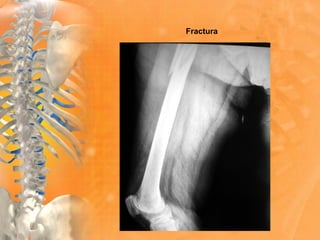

Fractura